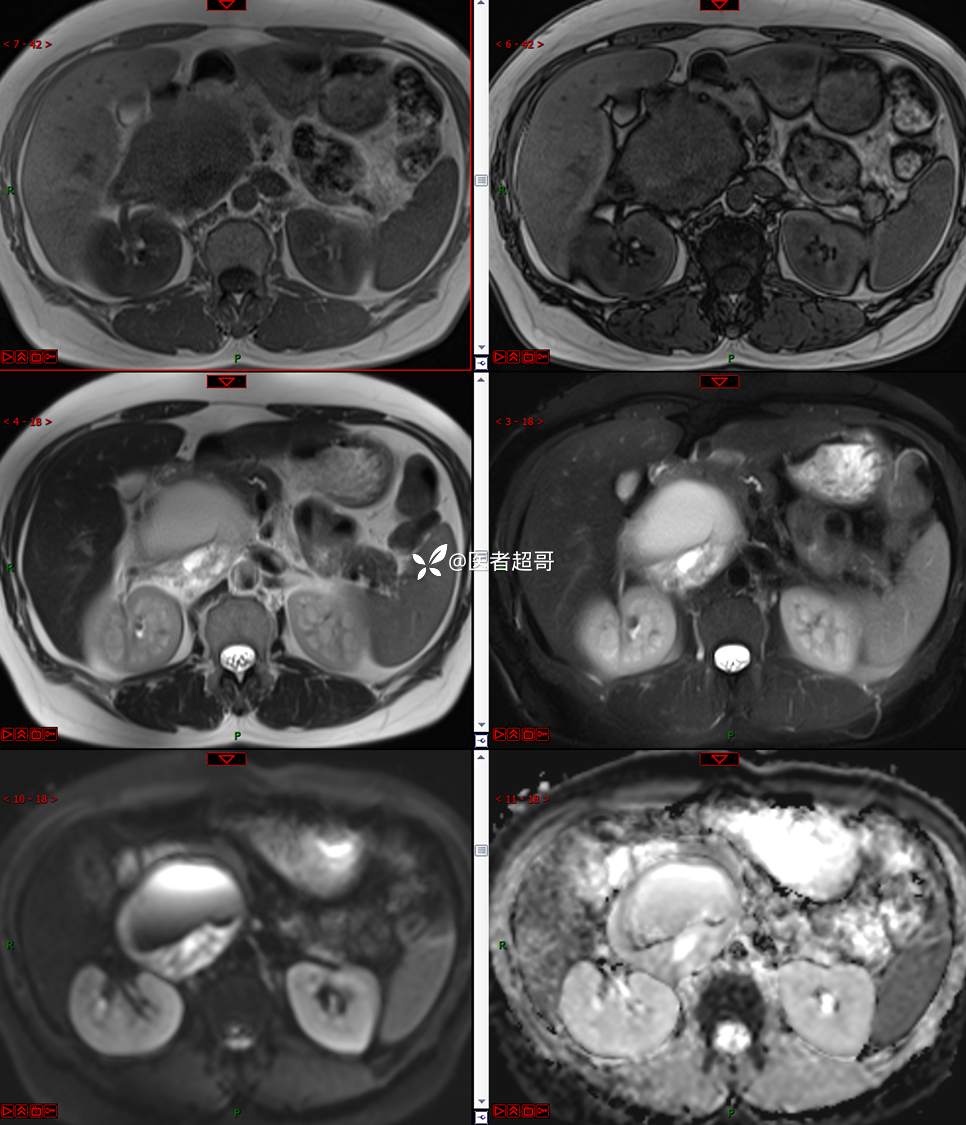

【影诊笔记671】定位有难度,究竟是腹腔内or腹膜后,请先定位,再定性!有结果~~~

hyy838 推荐女,52岁

主诉:查体发现腹部肿物1周。

现病史:患者1周前于我院查体发现右侧腹部肿物,无腹痛、腹泻、便血,无恶心、呕吐,患者为求进一步治疗,遂就诊于我院,门诊以“腹部肿物”收入院。患者自患病以来睡眠可,精神可,饮食可,小便无明显异常,体重无明显变化。

专科检查:腹部平坦,腹肌软,无压痛及反跳痛,无包块,肝脾无肿大,Murphy征阴性,腹部叩鼓,肝脾双肾无叩痛,移动性浊音阴性,肠鸣音正常。我院 肝胆胰脾肾彩超提示:脂肪肝、腹腔内囊实性团块,建议进一步检查。